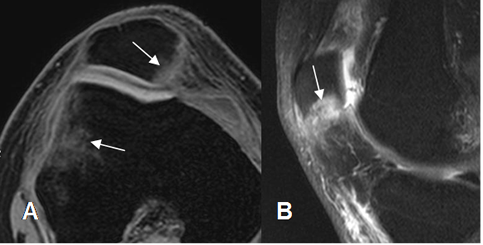

Fig 51. Contusión de la patela.

A: RM sagital en T1 y B: RM sagital en STIR. Trauma directo, con área hipointensa en T1 e hiperintensa en STIR, que corresponde a contusión. Existe hemartrosis asociada. (Flechas gruesas).